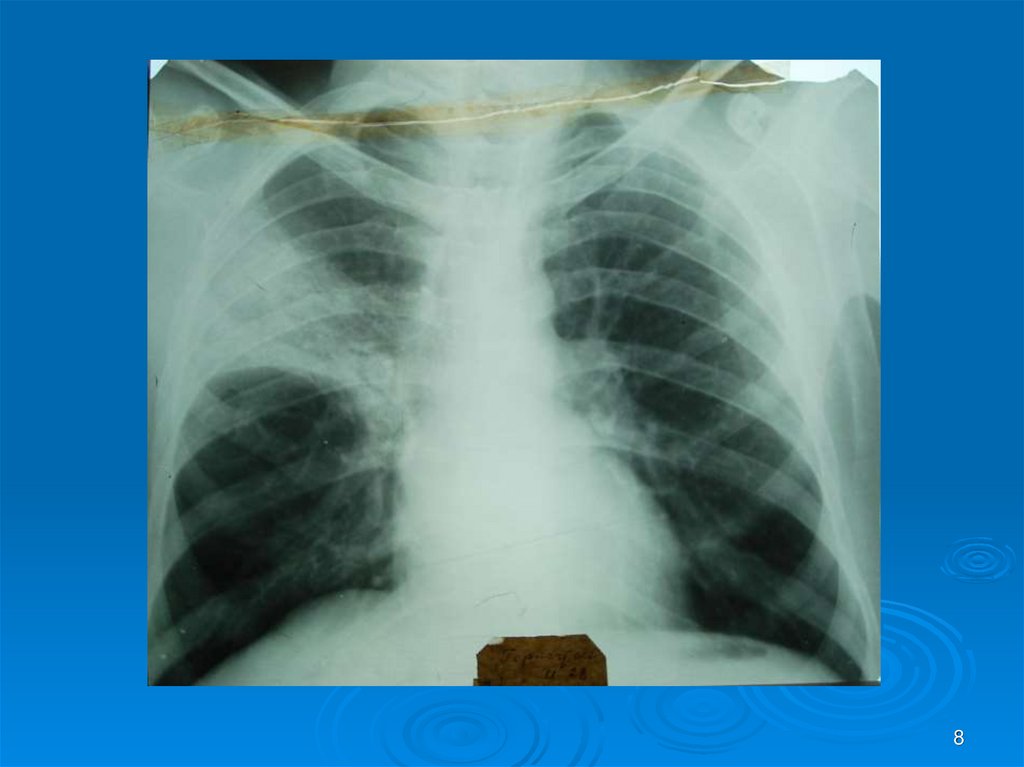

Каждый из вас должен интерпретировать Rснимки (всего 30) в ММ-презентации: назвать

заболевание, его локализацию, если осложнение

заболеваний – то указать какое. На снимках могут

быть пневмония (очаговая, сегментарная,

долевая), абсцесс легких I и II стадии, гангрена

легких, плеврит, ХОБЛ и сходные с ними болезни

легких, требующие дифференциальной

диагностики (туберкулез и др.). Успехов в работе!

8.

8